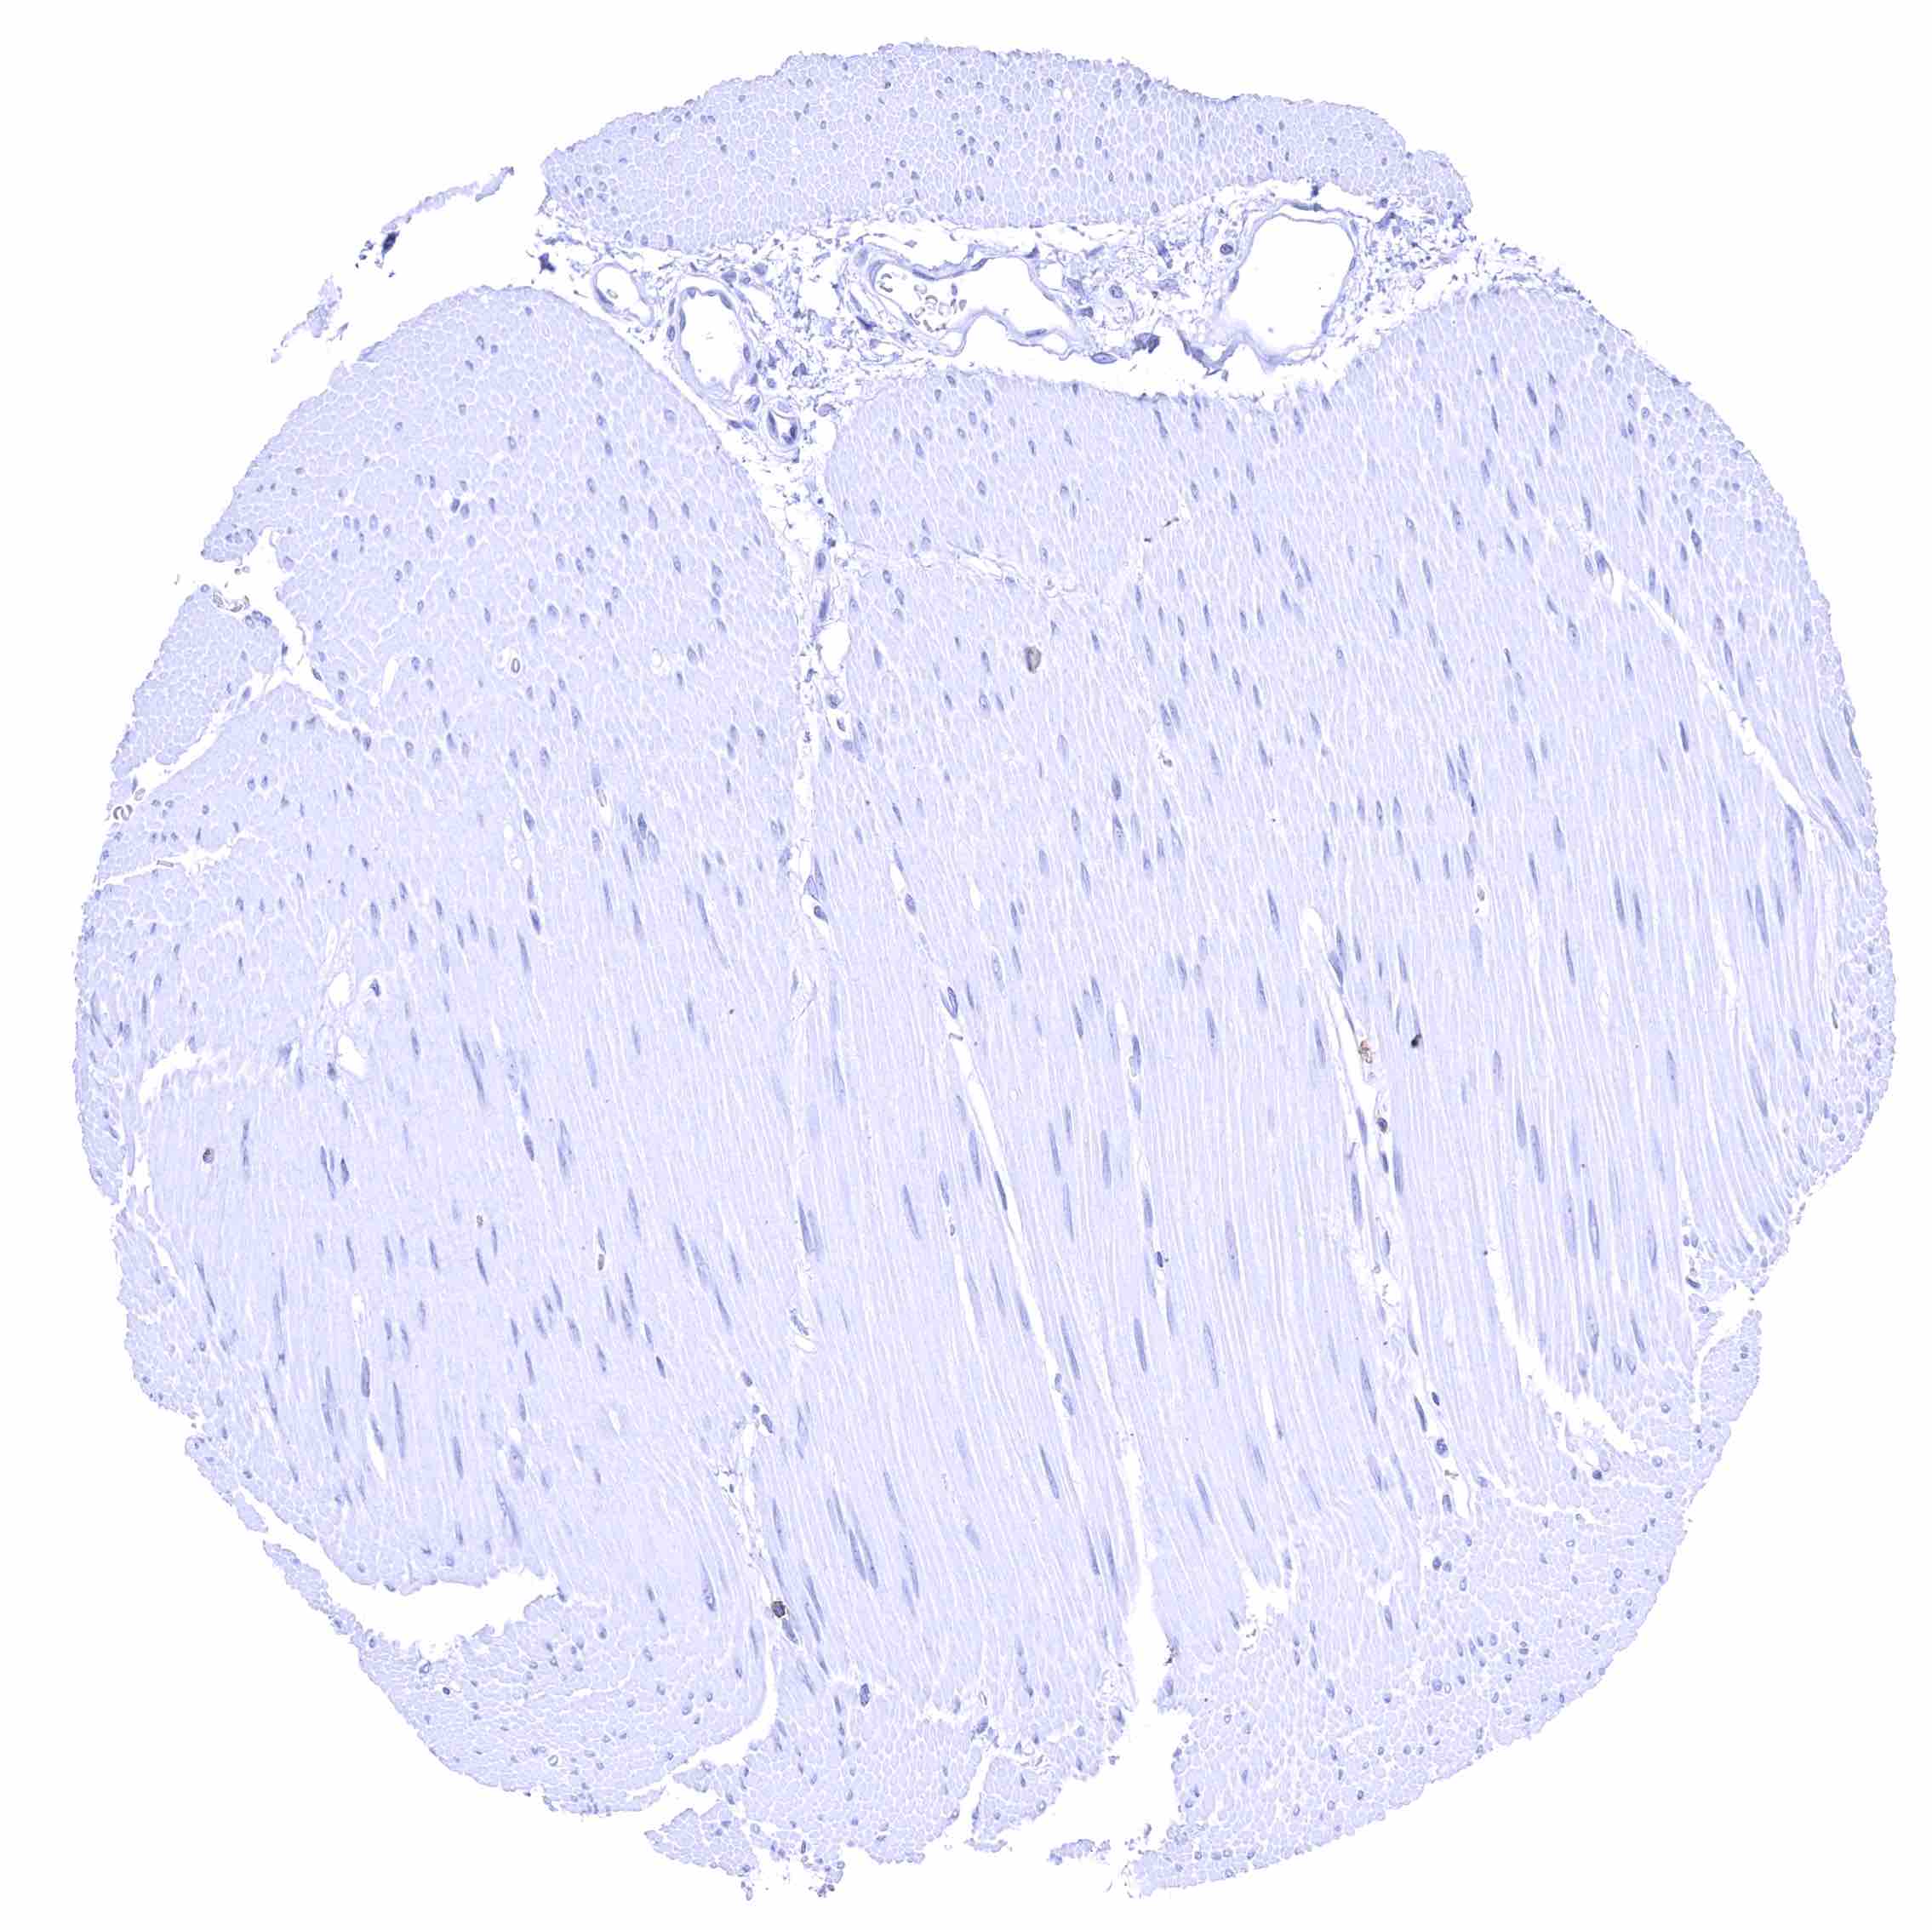

Heart muscle